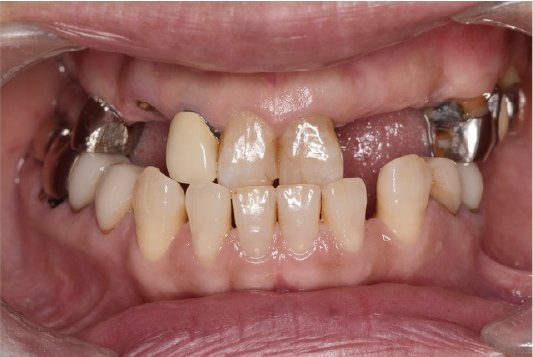

CASE02

■ 治療内容

上顎オールオン4インプラント治療(4本頬骨インプラント)

■ 治療費用

(モニター)3,330,000円(税込)

■ 治療期間

約10ヶ月

■ リスク

治療後の腫れや出血、またメンテナンスを怠ることで周囲炎のリスクあります。